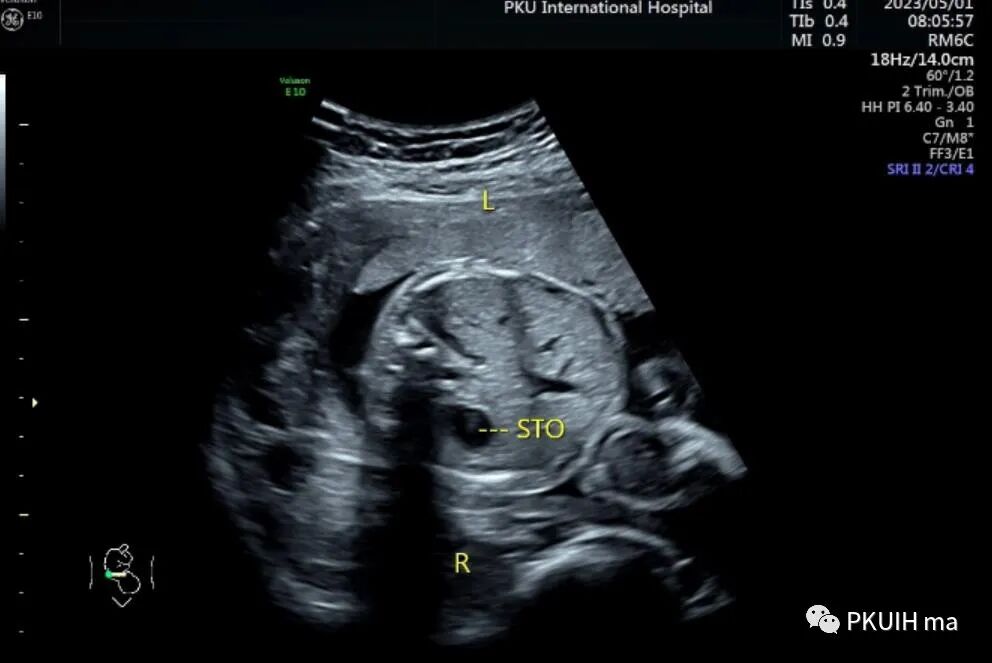

胎儿头位(右枕横位),胎儿小脑半球和脊柱均在右侧,采用右手法则判断近场为胎儿的左侧远场胎儿的右侧

胎儿胃泡位于右侧,肝脏和胆囊位于左侧,主动脉位于脊柱右前方,下腔静脉位于脊柱左前方